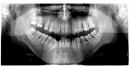

У меня заболевание дёсен – пародонтит. Я был на приёме у пародонтолога. Врач направил меня сделать панорамный снимок. Врач посмотрел снимок и сказал, что у меня пародонтит средней и местами тяжёлой степени, так как нет половины костной ткани. Назначил лечение: фотодинамическую терапию, плазмолифтинг – 4 сеанса и шинирование 4-х нижних зубов слева. Ещё он мне сказал, что нужно колоть уколы антибиотика.

Действительно ли нет половины костной ткани, то есть на половину зуба? Правильно ли назначено лечение? Нужно ли шинирование? Нужно ли применение антибиотиков? Не вредно ли это для дёсен?

По снимку определяется атрофия костной ткани. Все мероприятия приведут к временному улучшению. Рекомендуем вам обратиться к стоматологу-ортодонту или ортопеду для оценки состояния тканей и определения причины развития. Это может быть связано с перегрузкой, например.